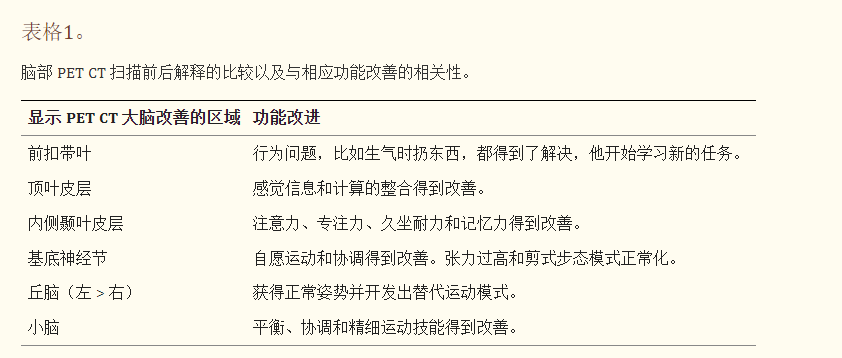

前扣帶回 (ACL)、頂葉皮層 (PC)、內側顳葉皮層 (MT)、基底神經節 (BG)、丘腦 (T) 和小腦 (C)。B 行)第一次移植后6個月后PETCT腦部掃描的干預后圖像顯示標記區域有所改善。藍色代表代謝減退區域。綠色代表正常的新陳代謝區域。圖A和B的比較顯示藍色區域顯著減少,綠色區域增加,這表明大腦的新陳代謝得到改善。

與之前的情況相比,他在矢狀面和額狀面上的體重變化有所改善;頭部、軀干和骨盆的排列也得到改善,雙側腿筋和小腿肌肉的緊繃感也有所減輕。患者開始執行雙手任務。在認知方面,由于他定期上學,他的注意力持續時間和久坐耐力也得到了改善。GMFM評分從60.67提高到67.75;GMFCS等級由Level3提升至Level2;和FIM評分從97分提高到99分。在比較第一次細胞治療之前和之后七個月期間進行的腦部PETCT掃描結果時,前扣帶葉、頂葉皮層、內側顳葉皮層、丘腦、基底神經節和小腦(表格1)。

這項研究表明,干細胞療法以及神經康復可有效改善腦癱患者的粗大運動功能和功能獨立性。自體BMMNC的多次移植后進行強烈的神經康復可加快神經再生過程,這反過來反映了患者殘疾水平和生活質量的積極結果。PETCT掃描可以有效地用于監測干預后細胞水平發生的變化。因此,多細胞療法是安全、可行的,并且可以有效地用作與CP的神經康復相結合的輔助治療。